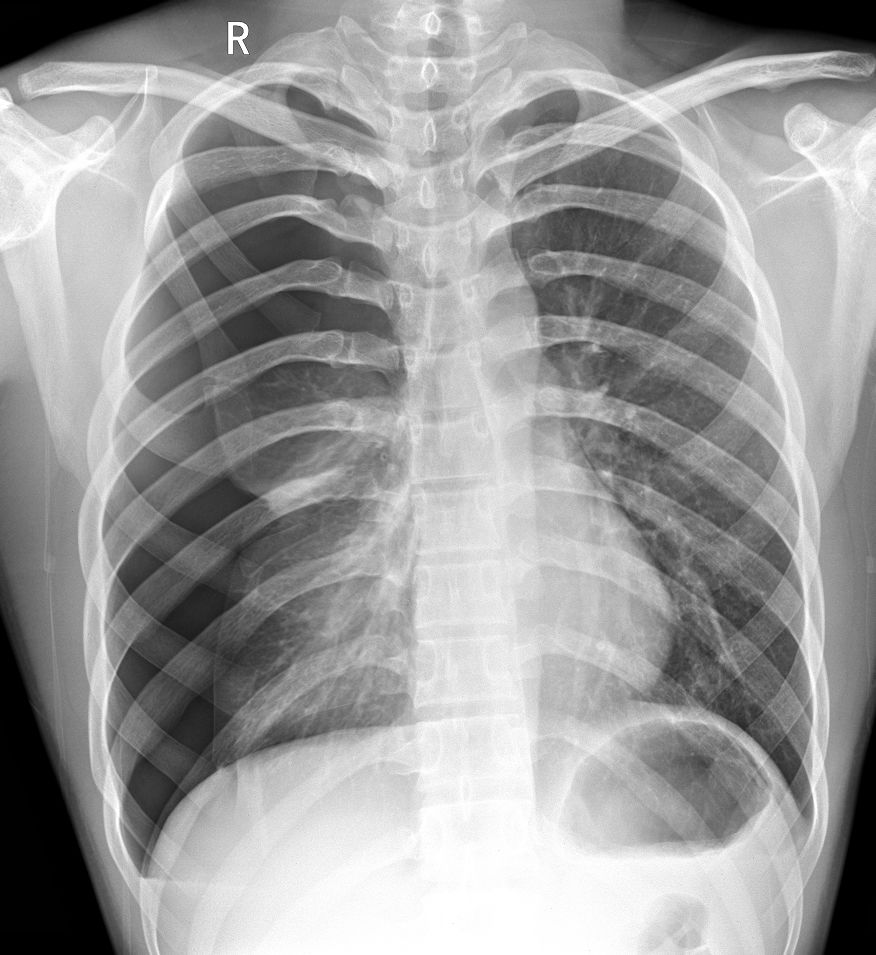

杨某,男,25岁,参加篮球比赛突发胸痛、呼吸困难,送医院检查。

病例6患者的X线胸片

患者右侧肺野内见带状异常透亮无肺纹理区,内侧缘可见发线状被压缩肺组织外缘(红色箭头),被压缩约75%以上,两肺门影不大,肋膈角清晰、锐利,心影形态、大小正常,纵隔稍向左移位。